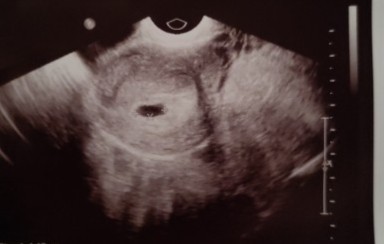

Ja z racji poprzedniej CP dzisiaj znowu byłam na USG, na poprzednim badaniu było widać malutki pęcherzyk, dzisiaj mamy pęcherzyk 1,37, ciałko żółte i zalążek płodu z migającym punkcikiem (pani doktor powiedziała, ze wyglada na serduszko ale jest za troszkę za wczesnie i za tydzień mam znowu się stawić na USG). Jestem taka szczeliwa, ze po przygodach wszystko jest póki co na dobrej drodze ❤️

Załączam zdjęcie dzisiejszej mikroskopijnej fasolki: